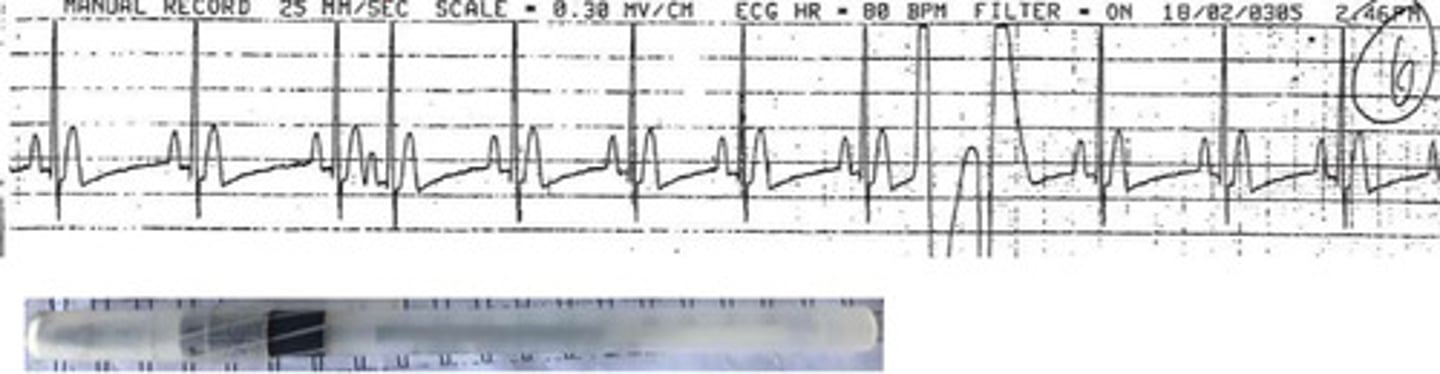

What arrhythmia is this?

Ventricular tachycardia

How would you describe the waves of this ECG?

1. Wide bizarre QRS

2. Monomorphic ventricular ectopic contractions

3. Absent P waves

How would you describe the rate and rhythm?

Regular rhythm with tachycardia